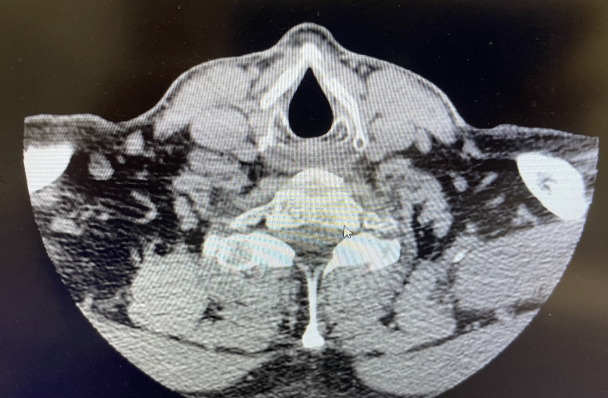

Foto de enmedio: forma de casa: luz glótica y cartílago tiroides que puede tener forma de lágrima o forma de reloj de arena.

Subglutis 3era foto huevito

TAC / AXIAL

NIVEL GLÓTICO:

CUERDAS VOCALES

Y CARTÍLAGO

TIROIDES